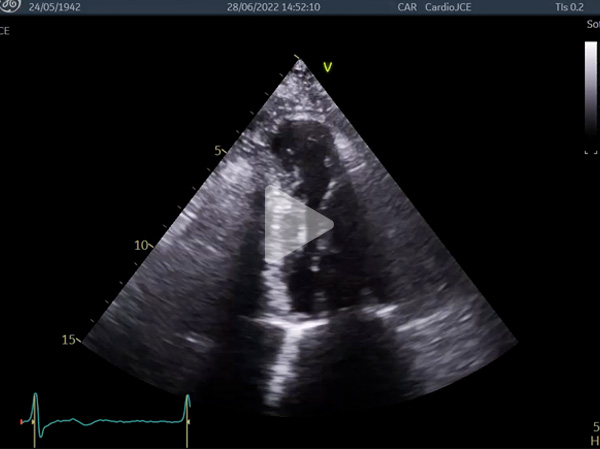

Vidéo 2 : anévrysme apical

- Anévrysmes apicaux décrits dans les CMH, mais généralement associés à des obstructions médio-ventriculaires 1

L’anévrysme apical : complication possible des CMH avec obstruction médio-ventriculaire ou apicale, associé à un risque élevé de mort subite rythmique et évènements thrombo-emboliques 3 :

- Dans notre cas l’hypothèse d’une embolie coronaire, en l’absence de notion d’obstruction ou de souffle